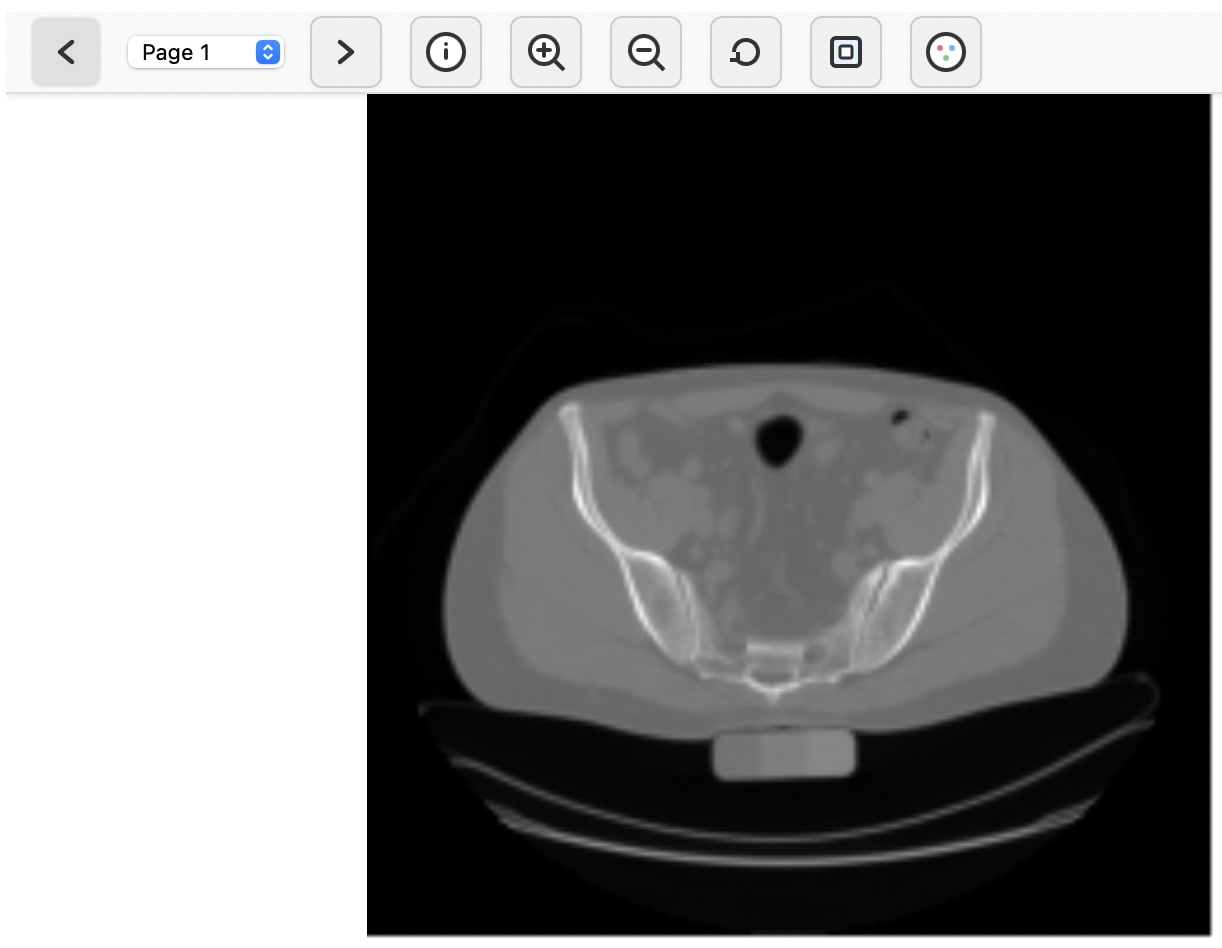

Galaxy’s built-in TIFF viewer can be used to roughly explore the image data. To do so, click on the galaxy-eye (eye) icon next to the output of the Clip image intensities ( Galaxy version 0.7.3+galaxy0) tool. This will bring up a basic user interface that shows a z-slice of the 3-D image, along with the option to navigate to a different slice along the z-axis (slices are presented as “pages”). The viewer shows the x-axis as left-to-right and the y-axis as top-to-bottom.

Galaxy's built-in TIFF viewer. Open image in new tab

Figure 1: Galaxy's built-in TIFF viewer.

The buttons in the toolbar can be used to zoom and pan the view, or this can be accomplished by using the scroll wheel or dragging the image with a pressed mouse button. Even though this viewer is very simple, we can make two important observations that provide some rough orientation within the image data that we are dealing with: